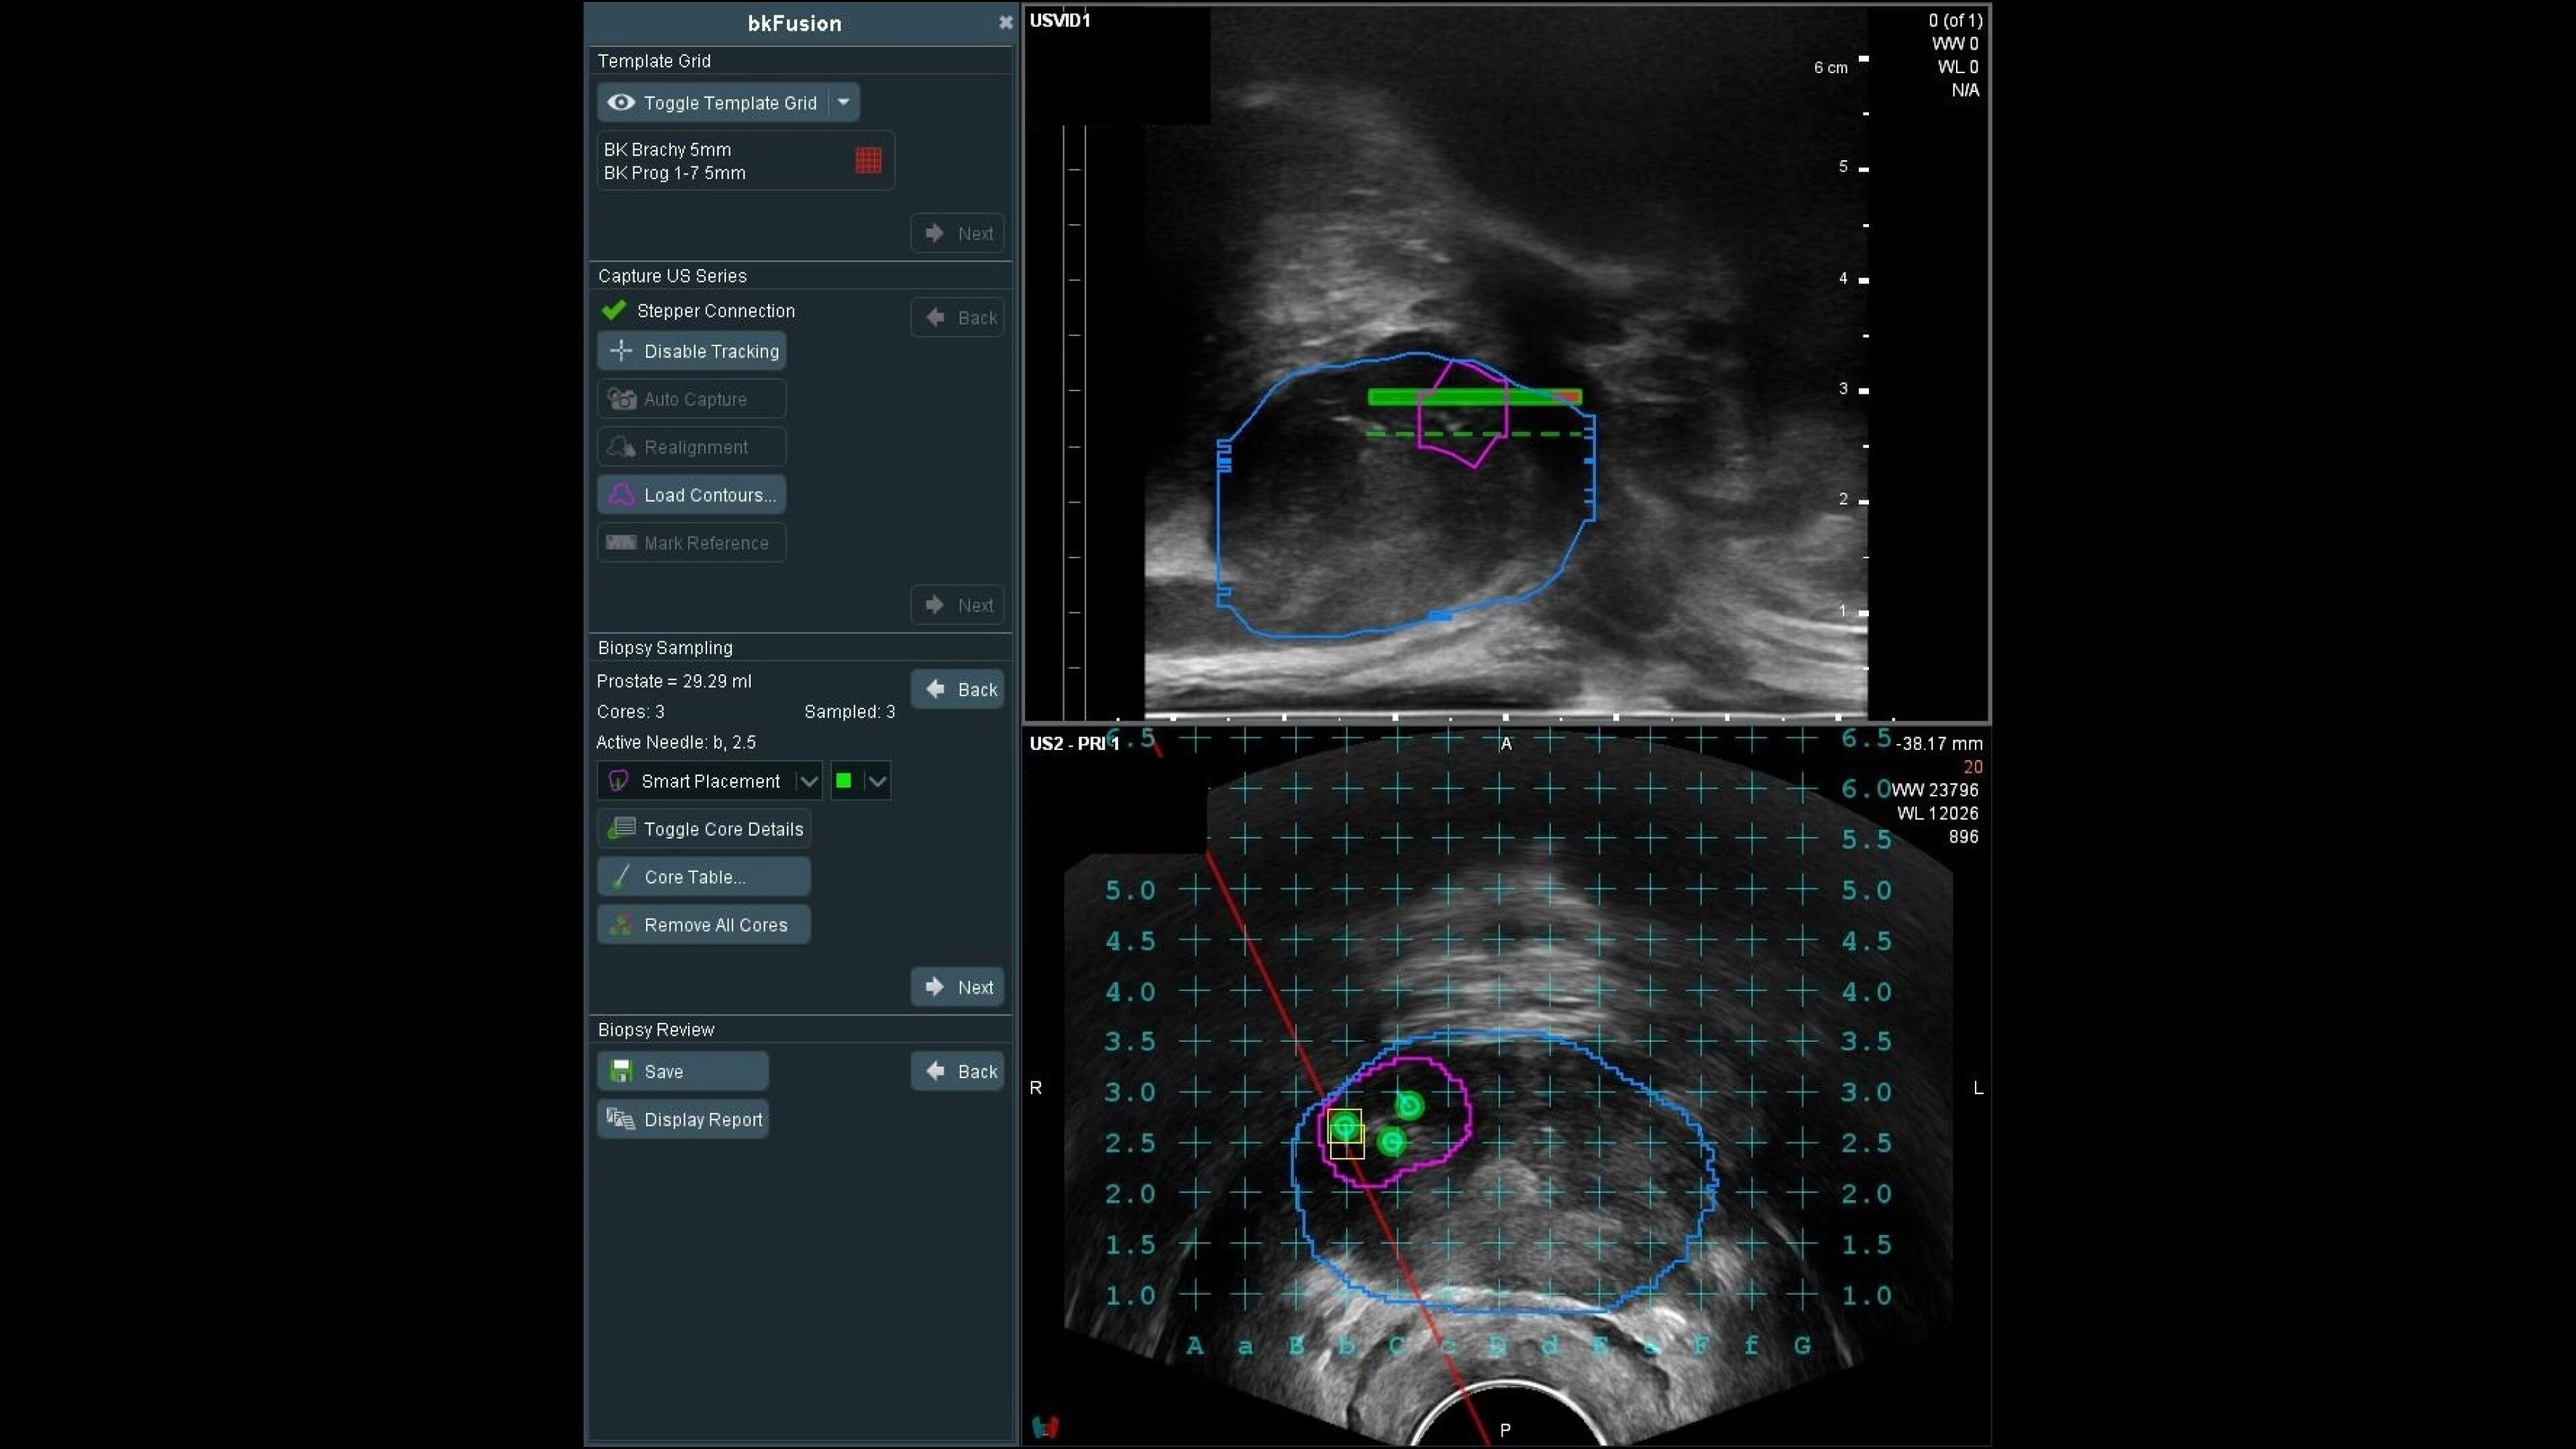

Explore versatile biopsy techniques with bkFusion

bkFusion evolves with your practice, offering transperineal stabilized and freehand, or transrectal endfire and sidefire techniques, supported by sterilizable transducers. The TP approach reduces infection risk and suits office or OR settings, showing high patient tolerability and negligible infection rates. Choose between freehand or stabilized approaches, with flexibility for office or OR settings.

Stabilized transperineal biplane transducer

Achieve precise biopsies with the stabilized transperineal biplane transducer and CIVCO EX3 Stepper.

Transrectal sidefire/endfire

Efficient biopsies with triplane and high-resolution endfire transducers. Integrated into a familiar transrectal workflow, compatible with freehand procedures and EM tracking.